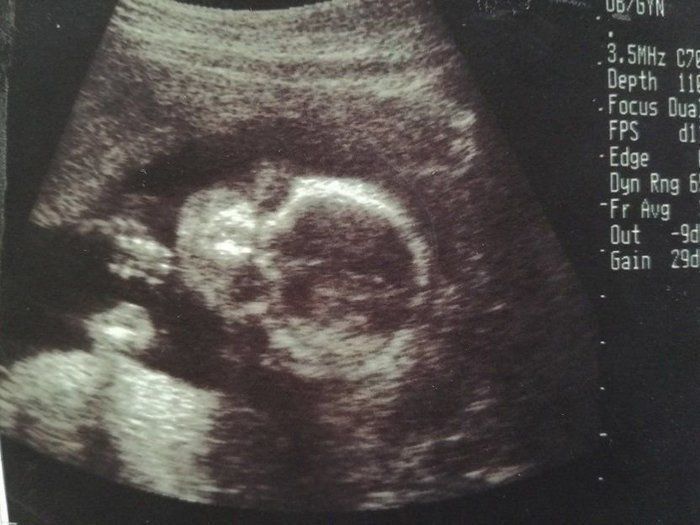

チャーミー小結さんの妊娠20週目のエコー写真

妊娠20週目の2D画像。横になった姿勢で、顔のアップの左側に写っている顎の細さが分かりました。赤ちゃんの推定体重345g。私の腹囲は人生初の90cm台になり、どこからみても貫禄充分なお母さんでした。